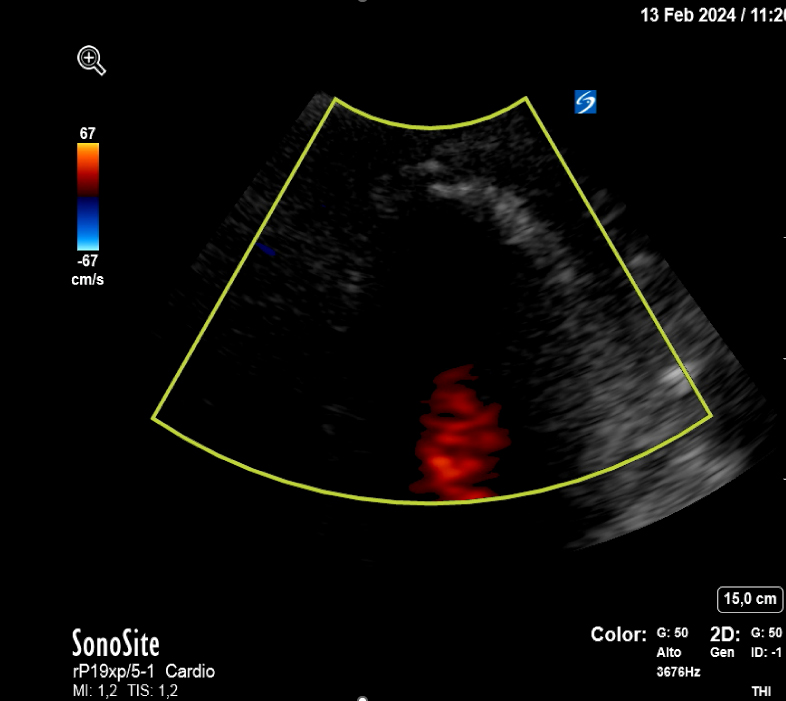

Se realiza interconsulta a Cardiología quien realiza una ecografía clínica cardíaca a pie de cama objetivando acinesia en ápex del ventrículo izquierdo con falta de continuidad a nivel septo-apical con flujo doppler compatible con rotura cardíaca a nivel de ápex que origina un derrame pericárdico moderado-severo, con colapso de ventrículo derecho.